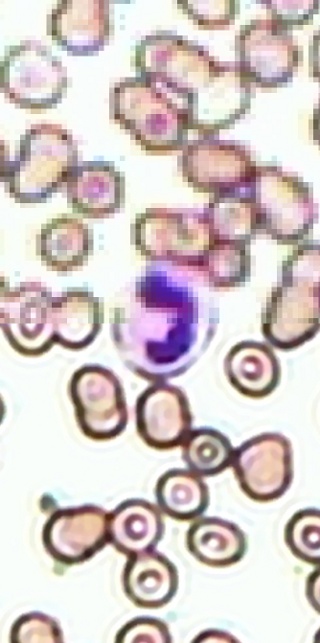

Unten: Anwendung von SR-Verfahren auf Mikroskopiedaten von Erythrozyten (rote Blutkörperchen, im Bild braun) und Leukozyten (weiße Blutkörperchen, im Bild violett). Zum Vergleich ist in der oberen Bildhälfte das Resultat durch bilineare Interpolation eines Eingabebildes gezeigt.